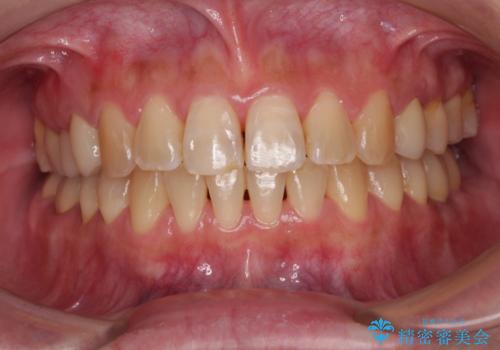

- 口元の突出感と口の閉じにくさを気にして来院された患者様です。

上下左右第一小臼歯4本を抜歯し、ワイヤー装置にて口元を引っ込めるよう矯正治療を行うこととしました。

ご友人などがびっくりするほど口元の突出感を改善することができ、患者様には大変満足していただきました。